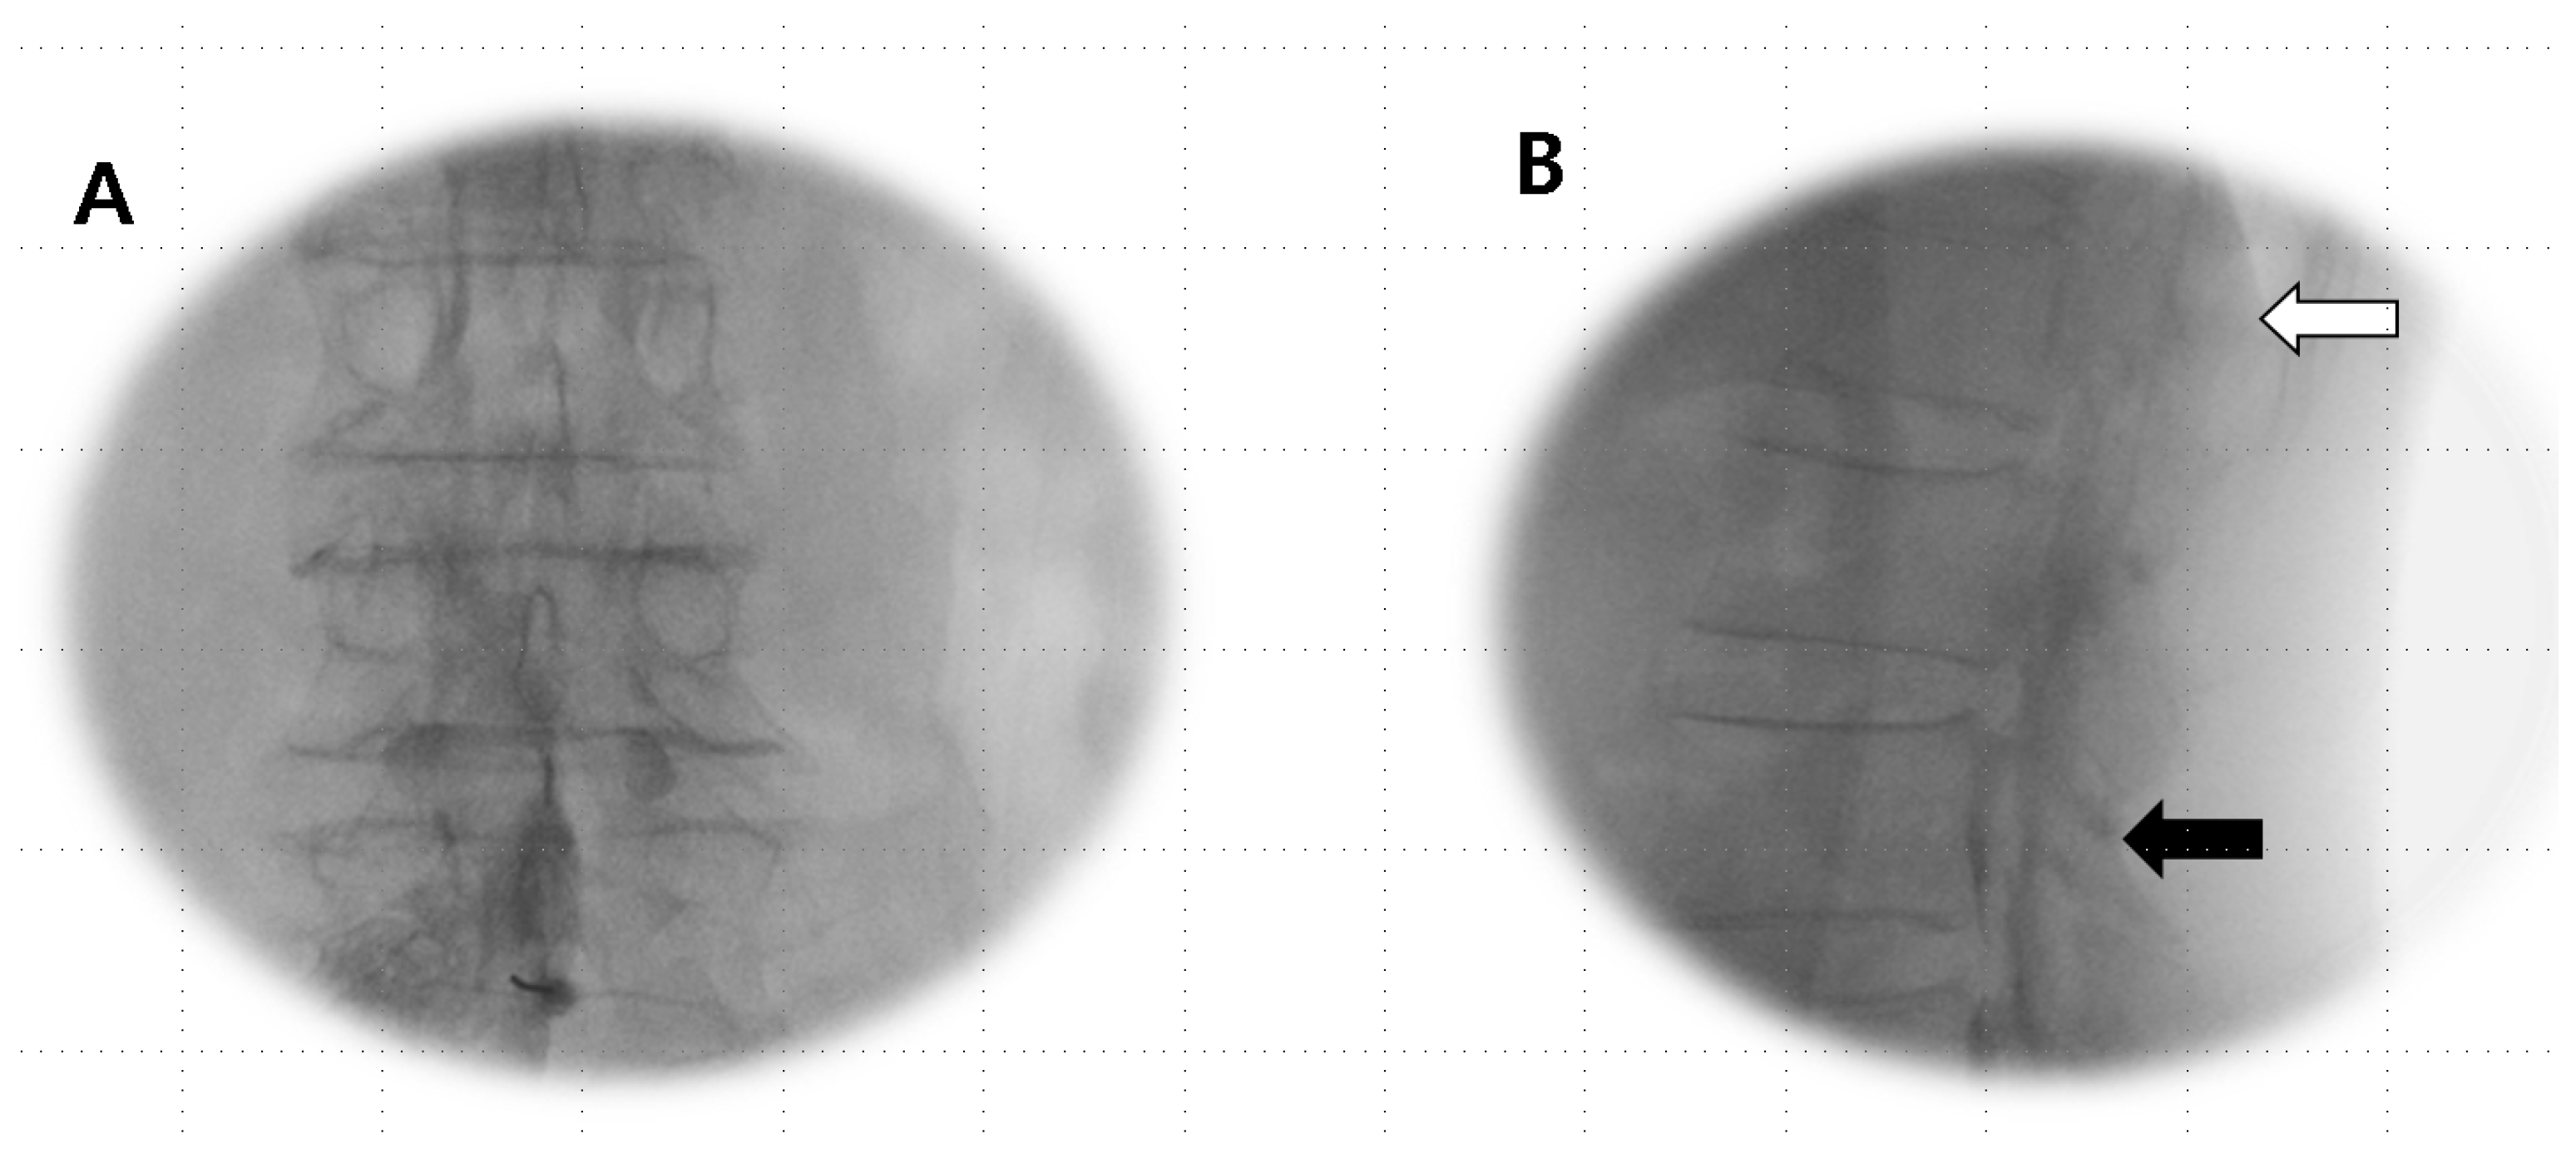

Anesthetics were administered if the Tuohy needle tip was situated within the epidural or subdural space (Figure 1A,B) or straddled between both spaces (Figure 2A,B).

Figure 1.

Subdural image. (A) AP view: a narrow column of contrast medium is confined to the central portion of the spinal canal and does not extend, outlining the exiting spinal nerve roots laterally. (B) Lateral view: the absence of CSF dilution and drainage; a longer duration persists, often remaining confined to the dorsal canal with a flat dorsal margin (dura mater) and an anterior bulging contrast (arachnoid mater) due to a smaller potential ventral subdural space.